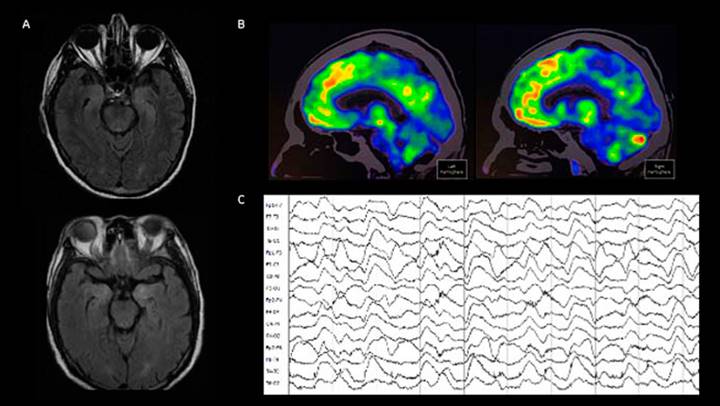

En la encefalitis anti-NMDAr, la imagen por resonancia magnética (IRM) cerebral puede demostrar hiperintensidades en la secuencia FLAIR en el lóbulo temporal medial, ínsula, tallo cerebral, ganglios basales o corteza (Figura 1). Ahora bien, hasta 50% de los pacientes puede tener una IRM normal.58 El electroencefalograma es anormal en la mayoría de los pacientes (85 a 90%), no obstante, sus hallazgos suelen ser inespecíficos (actividad lenta y desorganizada). En algunos casos, los registros pueden mostrar actividad epiléptica, focal o generalizada.58 Hasta en 30% de los pacientes con encefalitis antiNMDAr se ha descrito un patrón conocido como delta brush extremo (inglés, extreme delta brush)59 (Figura 1). Por otra parte, el análisis de LCR es anormal en 80 % de los pacientes al inicio de la enfermedad y en cerca de 90% en etapas posteriores,58 porcentaje que podría ser menor: una revisión sistemática de casos reportados estimó que solo 58% de los pacientes tenía LCR anormal.29 La ausencia de hallazgos no excluye el diagnóstico de psicosis de origen autoinmune, que en casos difíciles dependerá de la astucia del clínico tratante para continuar los estudios y mantener un alto índice de sospecha de acuerdo con el fenotipo clínico.60

Figura 1 A) Resonancia magnética cerebral ponderada en T2 FLAIR con cortes axiales a nivel del lóbulo temporal medial. Se observa incremento en la intensidad de señal de las cabezas de los hipocampos bilateralmente. B) 18-FDG PET demuestra un hipometabolismo occipital medial. C) Electroencefalograma con patrón extreme delta brush. Las imágenes pertenece a una mujer de 16 años con cuadro grave de encefalitis anti-NMDAr.

La tomografía por emisión de positrones con tomografía con 18-fluorodesoxiglucosa (18-FDG PET) puede considerarse cuando el diagnóstico de encefalitis autoinmune por anti-NMDAr no ha sido apoyado por otros paraclínicos y la sospecha de esta persiste clínicamente.61,62 En 18-FDG PET, la presencia de un metabolismo cerebral con gradiente fronto-occipital disminuido en regiones mediales de los lóbulos occipitales apoya el diagnóstico de esta enfermedad.61,62,63 Esta herramienta puede ser útil para el manejo diagnóstico y, al mismo tiempo, ser una técnica importante en la búsqueda de posibles tumores asociados, además el hipometabolismo occipital medial puede ayudar en el manejo y seguimiento de los pacientes con encefalitis anti-NMDAr62,63 (Figura 1).